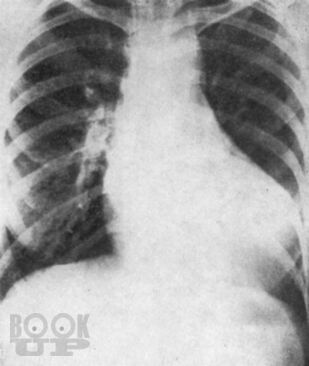

Монография всемирно известного автора посвящена вопросам клинической диагностики заболеваний сердца. Детально освещены общее исследование больного, сбор анамнеза и анализ жалоб, оценка симптомов, полученных при физикальном обследовании, а также при использовании рентгенологического и электрокардиографического методов. Для каждого заболевания автор выделяет решающие симптомы-“ключи”, помогающие установить точный диагноз.